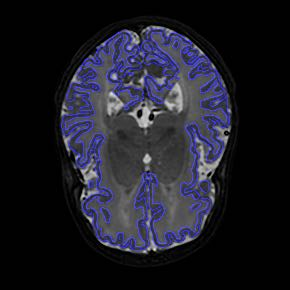

Fetal cortical plate segmentation is essential in quantitative analysis of fetal brain maturation and cortical folding. Manual segmentation of the cortical plate, or manual refinement of automatic segmentations is tedious and time-consuming. Automatic segmentation of the cortical plate, on the other hand, is challenged by the relatively low resolution of the reconstructed fetal brain MRI scans compared to the thin structure of the cortical plate, partial voluming, and the wide range of variations in the morphology of the cortical plate as the brain matures during gestation. To reduce the burden of manual refinement of segmentations, we have developed a new and powerful deep learning segmentation method. Our method exploits new deep attentive modules with mixed kernel convolutions within a fully convolutional neural network architecture that utilizes deep supervision and residual connections. We evaluated our method quantitatively based on several performance measures and expert evaluations. Results show that our method outperforms several state-of-the-art deep models for segmentation, as well as a state-of-the-art multi-atlas segmentation technique. We achieved average Dice similarity coefficient of 0.87, average Hausdorff distance of 0.96 mm, and average symmetric surface difference of 0.28 mm on reconstructed fetal brain MRI scans of fetuses scanned in the gestational age range of 16 to 39 weeks. With a computation time of less than 1 minute per fetal brain, our method can facilitate and accelerate large-scale studies on normal and altered fetal brain cortical maturation and folding.